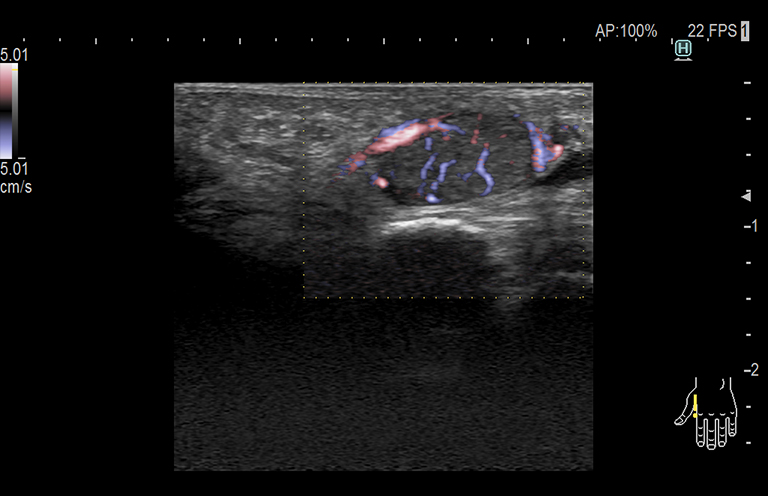

Aplicación: Mama

Función/análisis: eFLOW

Comentarios: Mama